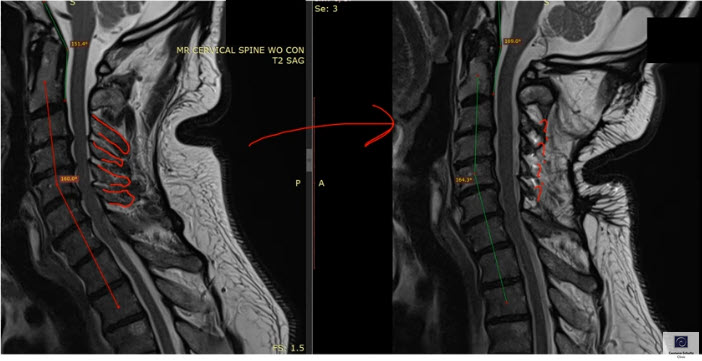

The surgeon went back to work and did a C3-C6 open door laminoplasty. This procedure involves cutting into the lamina and swinging the spinous process to the side. The spinous ligaments get moved over, as well. And the surgeon has to cut through the multifidus on one side in order to get to lamina.

Meanwhile, the structures on the Other side of the spine get scrunched up by the spinous process. In this case, everything from C3-C6 was pushed over to one side of the spine, so that the ligaments and multifidi did not perform their stabilizing function properly anymore.

As a result, the spinous ligament “suspension bridge” of the neck was now damaged, and the stabilizing spinous muscles were also damaged. In addition, the patient’s neck curve lost its natural curve and got noticeably straighter because of the loss of ligament stabilization of the neck.